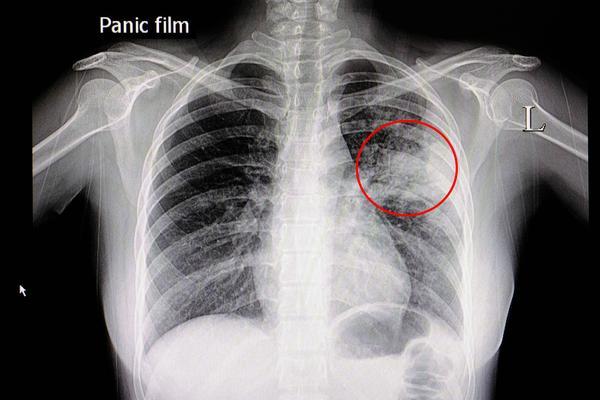

原创气管切开术后纵膈气肿气胸

图片尺寸1446x1782